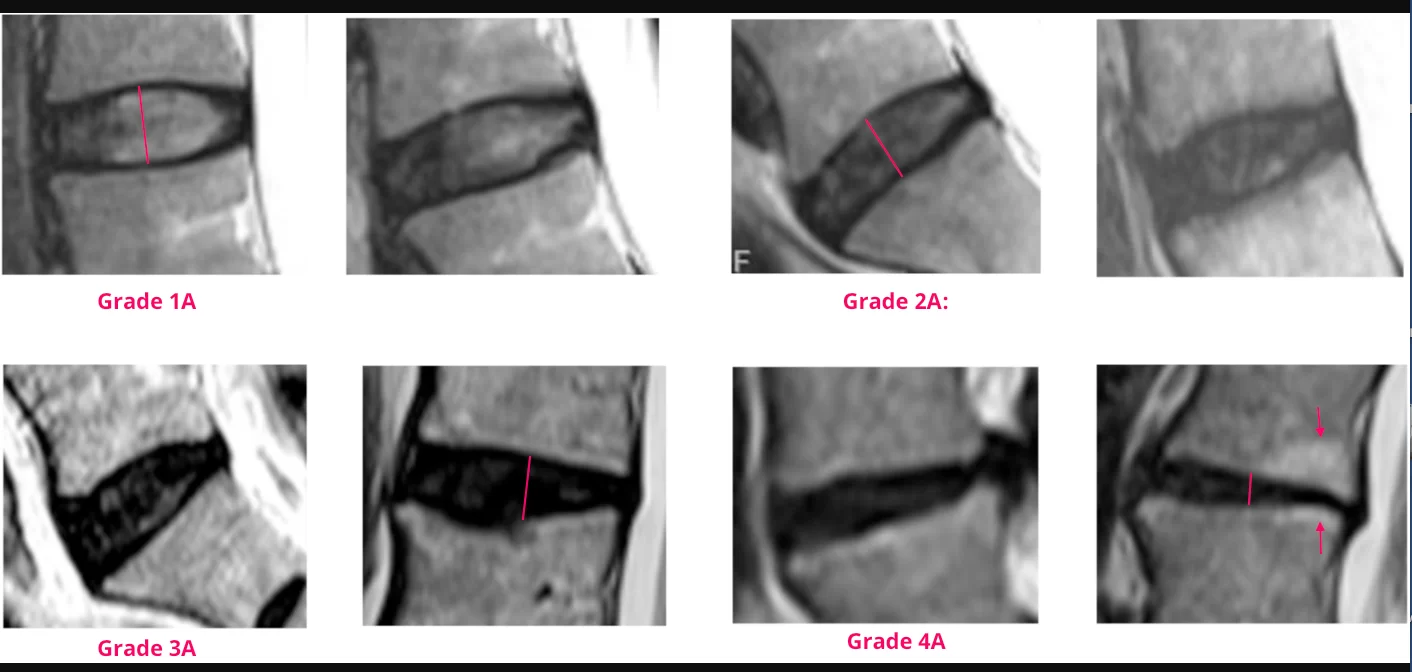

Diagnosticul herniei de disc necesită o combinație de discuții cu medicul, examinări fizice și teste imagistice. De cele mai multe ori, o scanare RMN este cea mai precisă metodă pentru a identifica hernia și a evalua severitatea acesteia. Alte teste, cum ar fi radiografiile sau tomografiile computerizate, pot fi utilizate pentru a exclude alte probleme, iar electromiografia ajută la identificarea nervilor afectați.